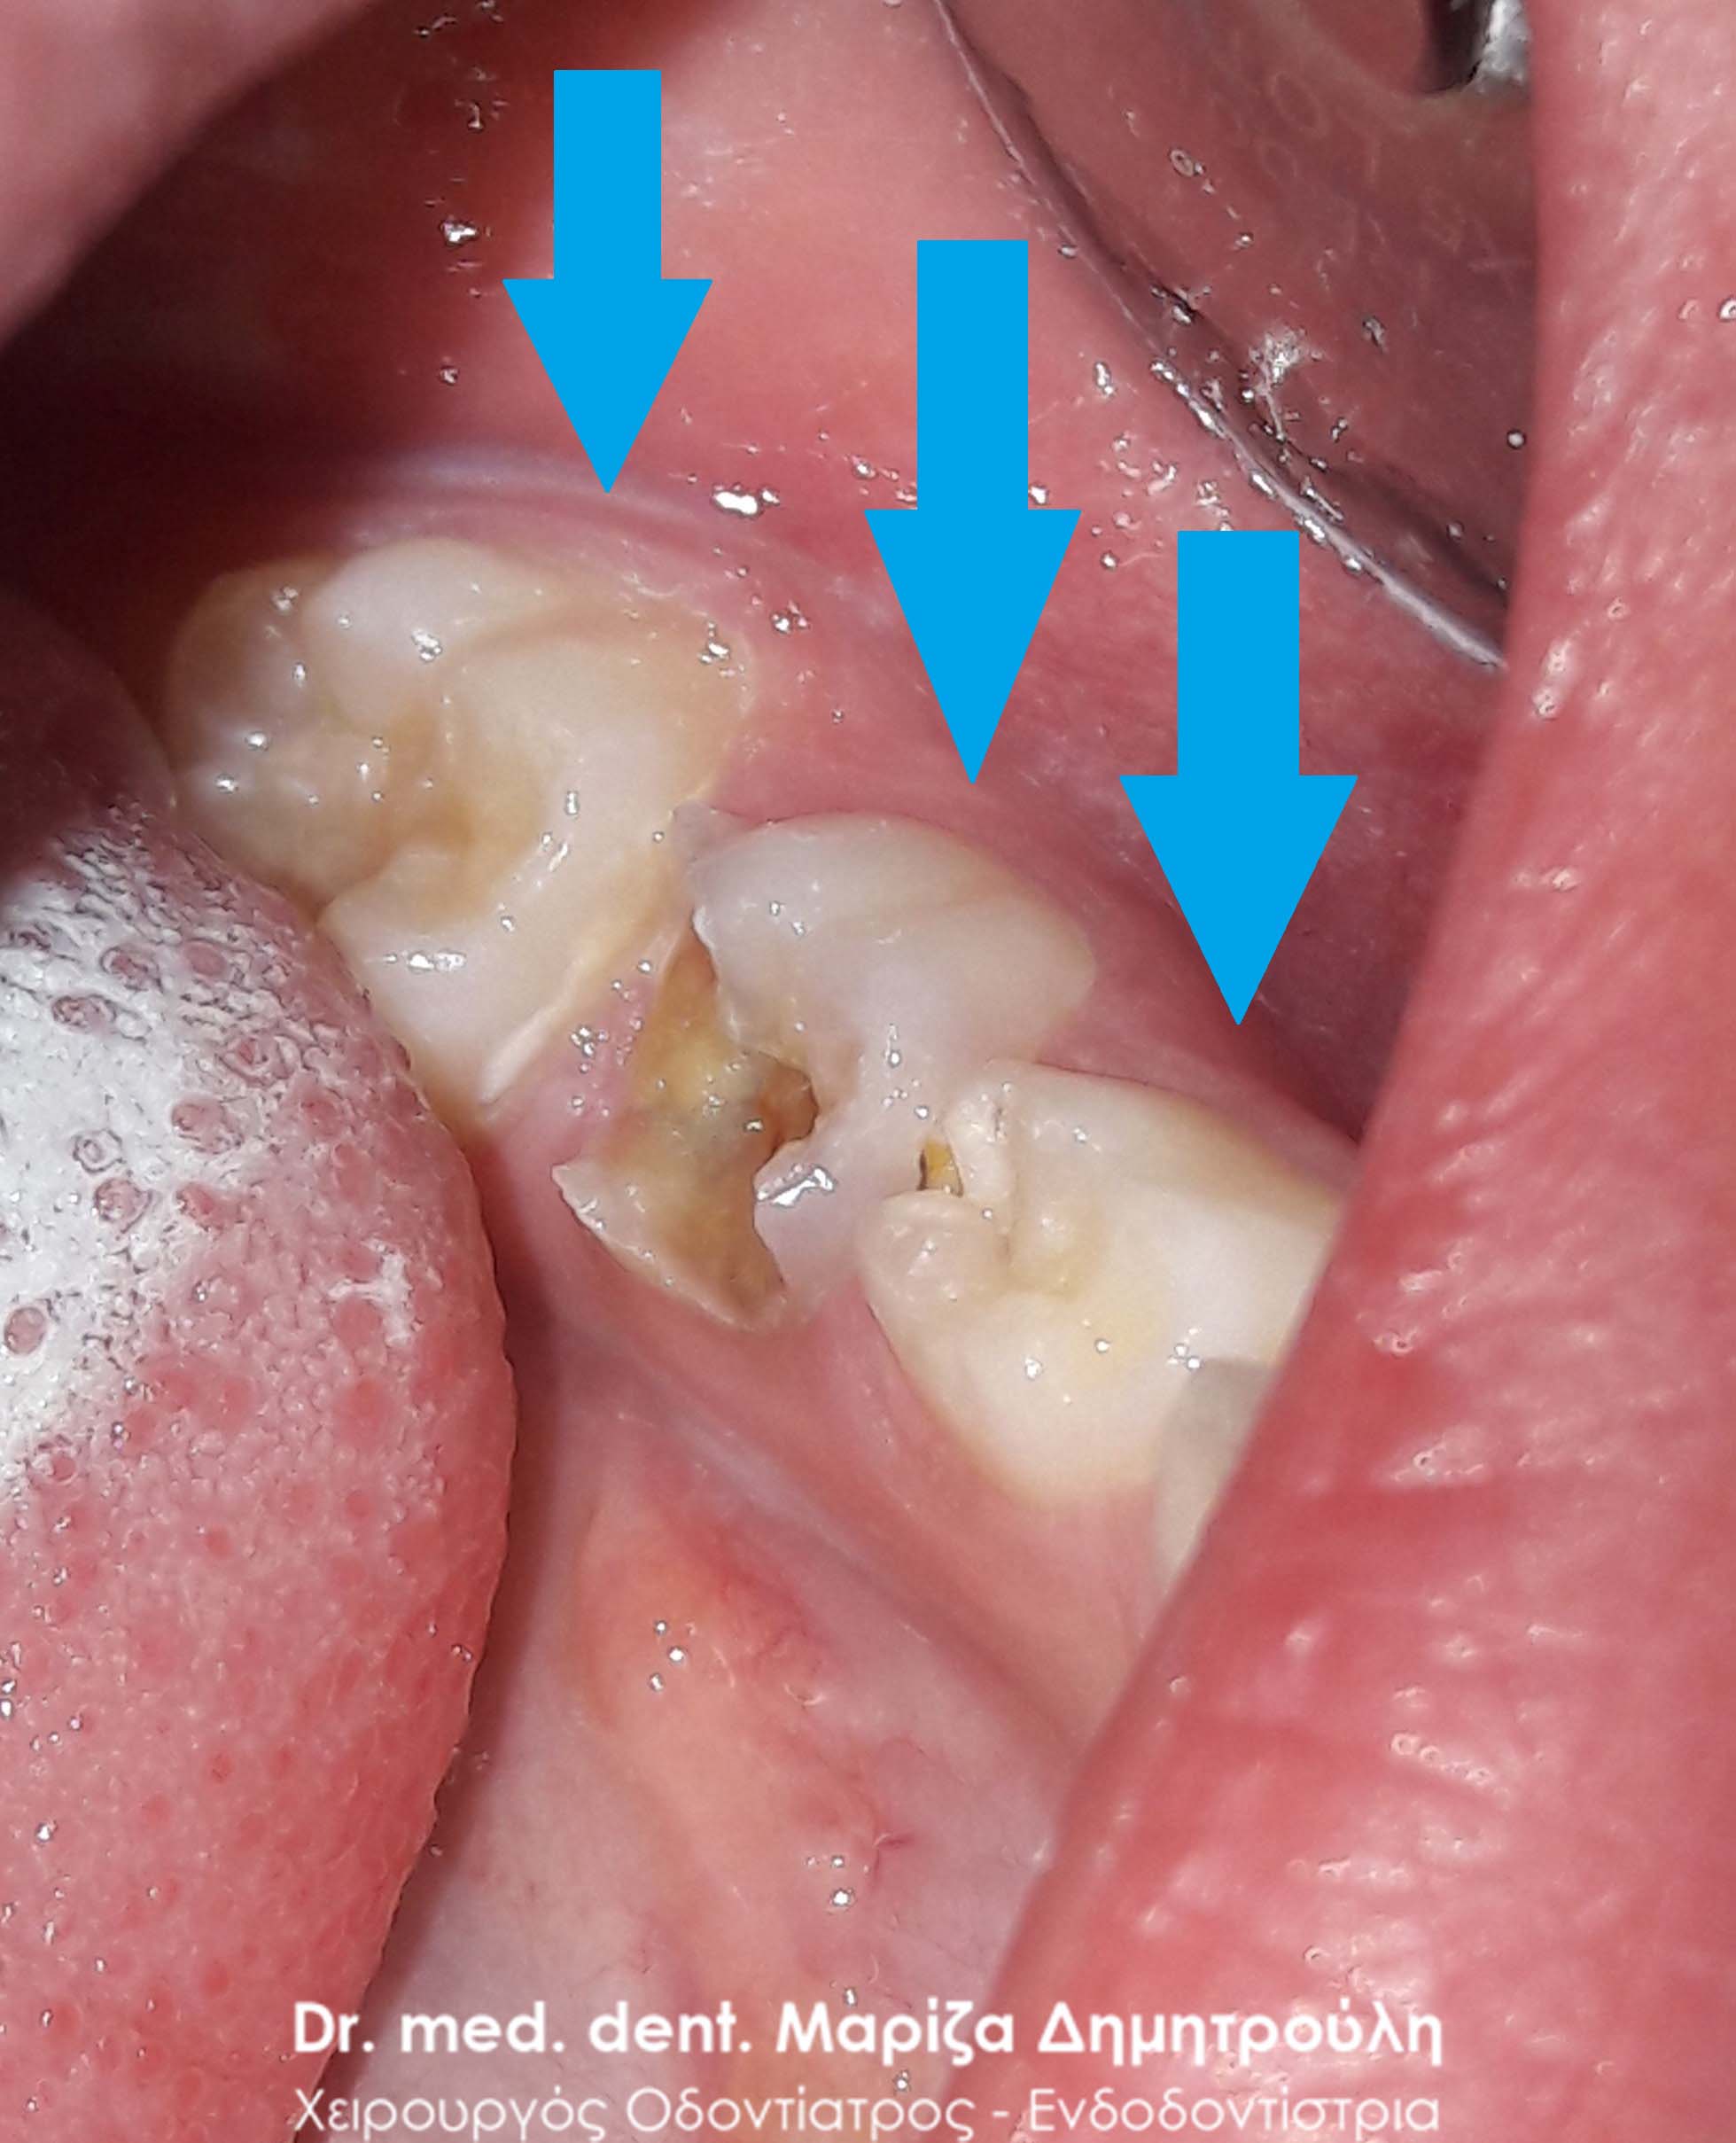

Η μικρή ασθενής ταλαιπωρείται από πόνο στην κάτω αριστερή μεριά της κάτω γνάθου. Μετά την κλινική εξέταση διαπιστώθηκε η ύπαρξη μιας μεγάλης τερηδονικής κοιλότητας στο κάτω δεύτερο αριστερό νεογιλό γομφίο και μίας μικρότερης στον αριστερό κάτω νεογιλό γομφίο

Μετά τη χορήγηση της τοπικής αναισθησίας απομακρύνθηκαν οι τερηδονισμένοι οδοντικοί ιστοί και οι κοιλότητες αποκαταστάθηκαν με λευκό σφράγισμα ρητίνης. στο πρώτο μόνιμο γομφίος της ίδιας πλευράς τοποθετήθηκε sealαnat για προληπτικούς λόγους.

ΠΡΙΝ

ΠΡΙΝ